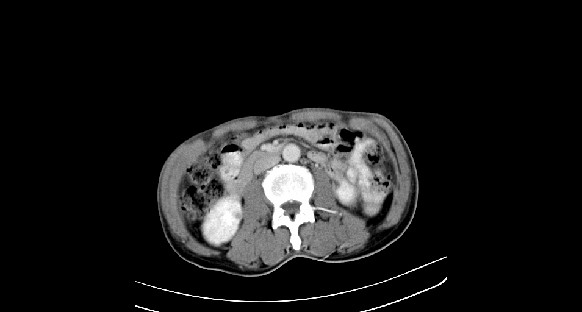

男性,70岁,体检b超发现左肾占位,请各位战友发表一下观点

左肾有两个病灶,且较大的病灶内可见点状钙化灶,增强扫描边缘也是呈渐进性强化,中央部分未见明显强化

考虑左肾脏错构瘤可能,不除外肾癌。

肾癌较肾aml可能大,建议mri,若t2明显高信号者则肾癌基本诊断明确。